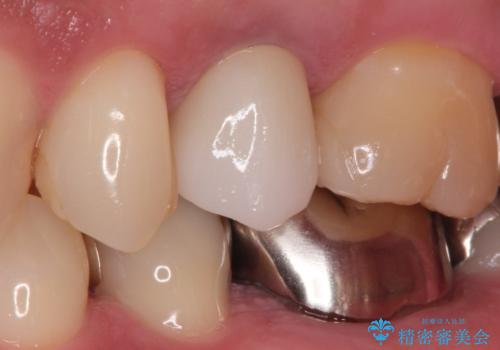

[根管治療・セラミック補綴] 歯ぐきを押すと痛い

![[根管治療・セラミック補綴] 歯ぐきを押すと痛いの症例 治療後](https://seimitsushinbi.jp/wp/wp-content/uploads/2020/06/f06e35140e887def91fb23d77e0ff069-500x350.jpg?v=1591340046)